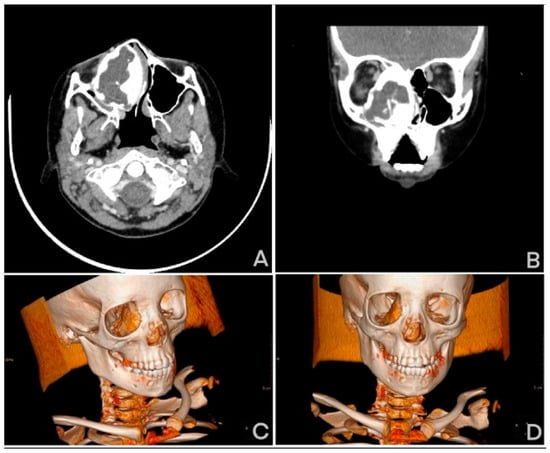

2. Case Description